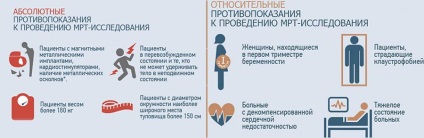

Ellenjavallatok eljárás

Átfogó képalkotó az egész test, valamint a más fajták, van egy szabványos ellenjavallat. Így a mágneses rezonancia nem ellenőrzik az emberek beültetett orvostechnikai eszközök:

- hallókészülékek;

- neurostimulator;

- inzulinszivattyúkra;

- pacemaker.

Nem ajánlott, hogy nézd meg az egész test MRI betegeknél alakult fém koronák, nem kivehető fogsor, tányérok, konzolok és csavarok, hogy tartsa a csontváz csontjai. Nem teszteltük a mágneses mező és a frissen operált betegek ragasztására lágy szövetek használt fém kapcsok (például műtét után aranyér Longo módszer).